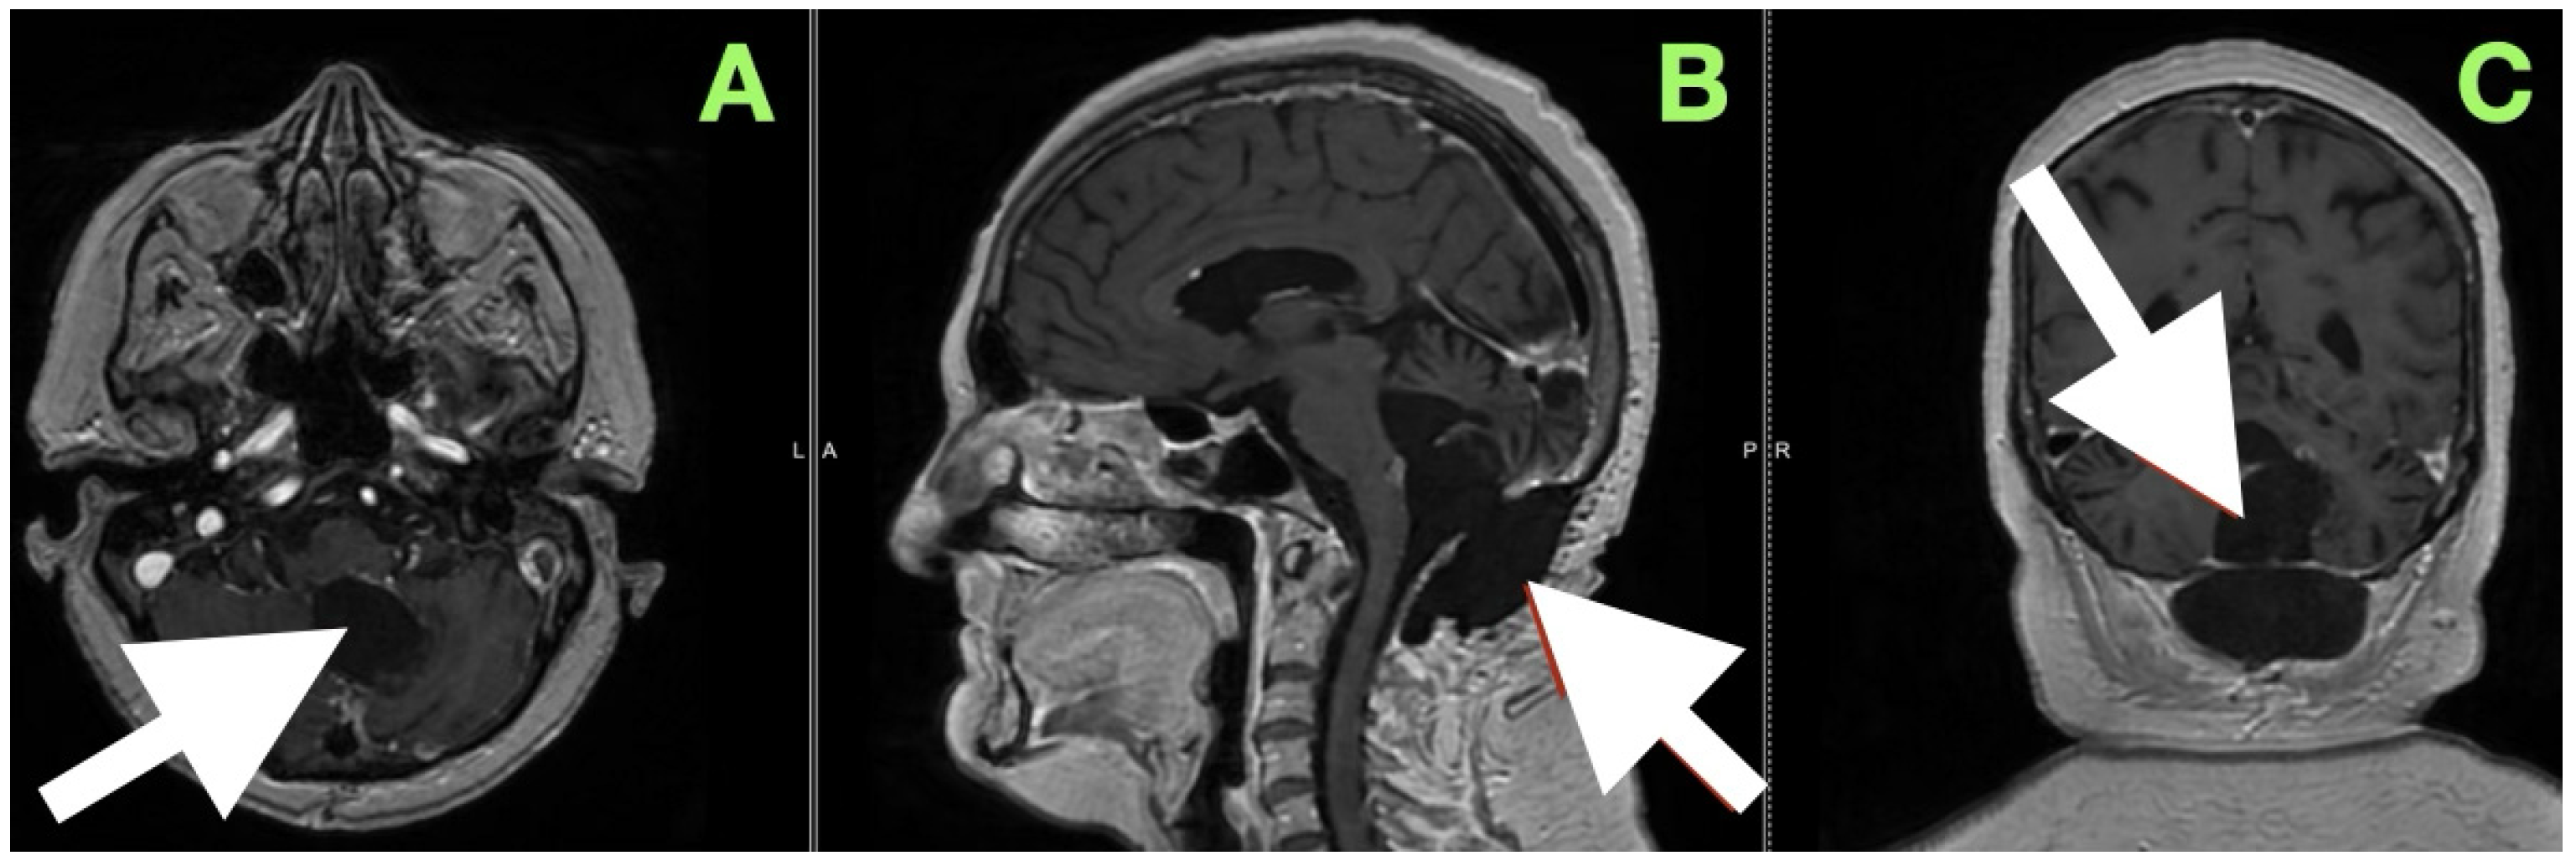

An immediate postoperative MRI (Figure 4) was performed to assess the resection extent and surgical purpose. Multiplanar T1-weighted sequences showed a sharply demarcated postoperative cavity; the fourth ventricle had expanded, all cerebrospinal fluid paths were unobstructed, and there was no abnormal enhancement seen. The imaging findings served as direct visual proof for the intraoperative aims, namely, decompression of the brainstem, anatomical re-establishment of the cisterns, and maintenance of surrounding neurovascular structures. No perilesional edema and no hemorrhagic debris support the use of the “stay-at-anatomy” dissection approach. Near-total resection with a midline suboccipital telovelar approach accomplished complete decompression, anatomical restoration, and preservation of all appropriate neurovascular structures. Immediate postoperative MRI demonstrated no residual mass effect or abnormal enhancement, with no imaging assessment of keratinaceous content, despite the fact that there was microbiologically adherent capsular remainder on the ventricular floor that was purposefully left intact.

Her mobilization was slow; however, by day four postoperative, she was ambulatory (i.e., independent), demonstrated dynamic balance with a better regard for spatial awareness. Her speech clarity overall remained normal, and there were no signs of bulbar compromise. An initial follow-up CT scan performed one week postoperatively (Figure 5) reaffirmed what was visually apparent at bedside: her fourth ventricle was entirely re-expanded; cerebellomedullary cistern remained patent; and posterior fossa structures remained in a reconstructed relationship. Radiologically, there were no signs of residual mass, hemorrhage, infarct, or new hydrocephalus. The converging relationship of anatomical restoration evident on imaging and gradual, quantifiable neuro recovery demonstrated the value of performing a dissection aligned to more native anatomical planes, with the maintained surrounding structures.

At the three-month postoperative assessment, this case sought to document not only the anatomical outcome, but the durability of functional restitution. The neurological examination demonstrated stable and complete resolution of the neurological deficits that initiated the presentation. The truncal instability that preoperatively presented as a wide-based gait and inability to perform tandem steps without loss of balance was fully resolved. The patient maintained midline posture without compensatory sway, including while standing with eyes closed, suggesting that the midline cerebellar control was restored. A three-month follow-up showed the KPS score was 90 and the mRS score was one. Testing of limb coordination revealed smooth and uninterrupted performance on finger-nose-finger and heel-knee-shin maneuvers with no terminal dysmetria or rebound phenomena. The rapidly alternating movements were both symmetric and fluid, with the previously noted dysdiadochokinesia on the ipsilateral side disappearing. The preoperative ocular pursuit instability and intermittent nystagmus could no longer be elicited, with horizontal and vertical gaze steady, full, and conjugate, and the initiation of saccades being instantaneous. Bulbar function had returned to normal with clear speech, coordinated swallowing, and no choking or nasal regurgitation while drinking liquids. There were no long tract signs, sensory asymmetries, or pathologic reflexes, and muscle tone was physiologic in all extremities. The patient also reported uninterrupted sleep, no further vertiginous episodes, and no headaches, indicating a sustained normalization of ICP dynamics. Daily living had been resumed fully, including occupational demand, without any limitations or accommodations.

A magnetic resonance image performed at this time (Figure 6) sought to provide an objective confirmation of surgical and clinical impressions. The axial T1-weighted post-contrast image (Figure 5A) demonstrated a sharply marginated, extra-axial postoperative cavity occupying the midline posterior fossa, with preservation of surrounding parenchymal architecture and no pathologic enhancement to suggest residual epidermoid tissue. There was no gliotic signal change or loss of regional volume, and the normal folial pattern of both cerebellar hemispheres was intact. The sagittal post-contrast T1-weighted image (Figure 5B) demonstrated a fourth ventricle in appropriate anatomical alignments, with unobstructed continuity between the aqueduct of Sylvius, the ventricular outlet foramina, and the cerebellomedullary cistern. The relationships between the cerebellar vermis, brainstem, and dorsal medulla displayed anatomical preservation, with no features suggestive of postoperative adhesive arachnoiditis or CSF flow obstruction.

Figure 4. Immediate postoperative MRI. (A) Axial, (B) sagittal, and (C) coronal T1-weighted images show a postoperative cavity with complete re-expansion of the fourth ventricle and patent CSF pathways (white arrows). No abnormal enhancement or diffusion-restricted focus is present, confirming gross total resection and restoration of posterior fossa anatomy.

Figure 6. Three-month postoperative contrast-enhanced MRI documenting stable anatomical restoration and absence of residual lesion. (A) Axial post-contrast T1-weighted image shows a sharply delineated postoperative cavity in the midline posterior fossa, with preserved cerebellar hemisphere contour and absence of abnormal enhancement. (B) Sagittal post-contrast T1-weighted image demonstrates a fully re-expanded fourth ventricle, patent CSF pathways, and stable alignment of posterior fossa structures, without recurrence or postoperative complication.